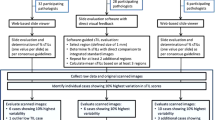

Haematoxylin and eosin (H&E)-stained histological slides from formalin-fixed paraffin embedded (FFPE) pre-treatment core biopsies and tumours resected at surgery were requested from all centres for central review and digitization. Image analysis was conducted by AD at the Institute of Astronomy in Cambridge, as part of a collaboration with Oncology [17]. Our image-processing pipeline is summarized in Fig. 1. Our approach is entirely automated and consists of identifying tissue for analysis, segmenting cell nuclei and finally using machine-learning to classify nuclei as cancer, stromal or lymphocyte based on a training set. Adipocytes were included in the stromal category because based on nuclear features alone, it was not possible to reliably identify them. Further details are provided in Additional file 1.

Overview of the image processing method. a Full-face H&E scanned images consist of four levels (L0–L3) across a gradation of resolutions. The levels L3 (lowest resolution) and L0 (highest resolution) are used to process each image. b Automated identification of regions of interest was performed by dividing image layer L3 into several small blocks (grid) and by analysing the pixel intensity distribution of each block. c Each image block found to contain tissue was mapped onto layer L0 and image segmentation and object detection (green ellipses) was conducted to construct an object catalogue. d Illustrative representation as a contour map of lymphocyte density derived using a k-nearest neighbour algorithm of the 50 nearest like-class neighbours. e Distribution of lymphocyte metrics by categories of lymphocytic infiltration based on central pathology review. SVM support vector machine

On average, each patient’s tumour or residual tumour bed was represented in 1.2 pre-treatment slides (range 1–23) and 1.8 slides from the post-treatment surgical specimen (range 1–35). Figure 1 summarizes our novel image processing pipeline: scanned slide images were extracted as four layers differing in their size and resolution, and using the lowest resolution image, areas that contained tissue were automatically identified and white space was excluded from further analysis. Next, using the highest resolution layer, single cell nuclei were detected, and using a support-vector-machine (SVM) approach trained using around 1,000 objects per class, cells were sub-classified into readily distinguishable categories (cancer, stromal or lymphocyte). Metrics relating to these three cell types and describing absolute cell number (count), relative cell type proportion (fraction) and density (minimum, median and maximum) based on the 50 nearest like-class neighbors, were computed. That is, every detected cell was assigned a density estimate based on the distance between it and the 50 nearest cells of the same type. Pathologist assessment of lymphocytic infiltration in pre-treatment biopsies with paired automated data, to which the pathologist was blinded, was available for comparison in 377 samples. All automated metrics of lymphocytic infiltration were significantly associated with pathologist scores (p <0.0001 for all three comparisons; Fig. 1), attesting to the validity of the automated image analysis approach.